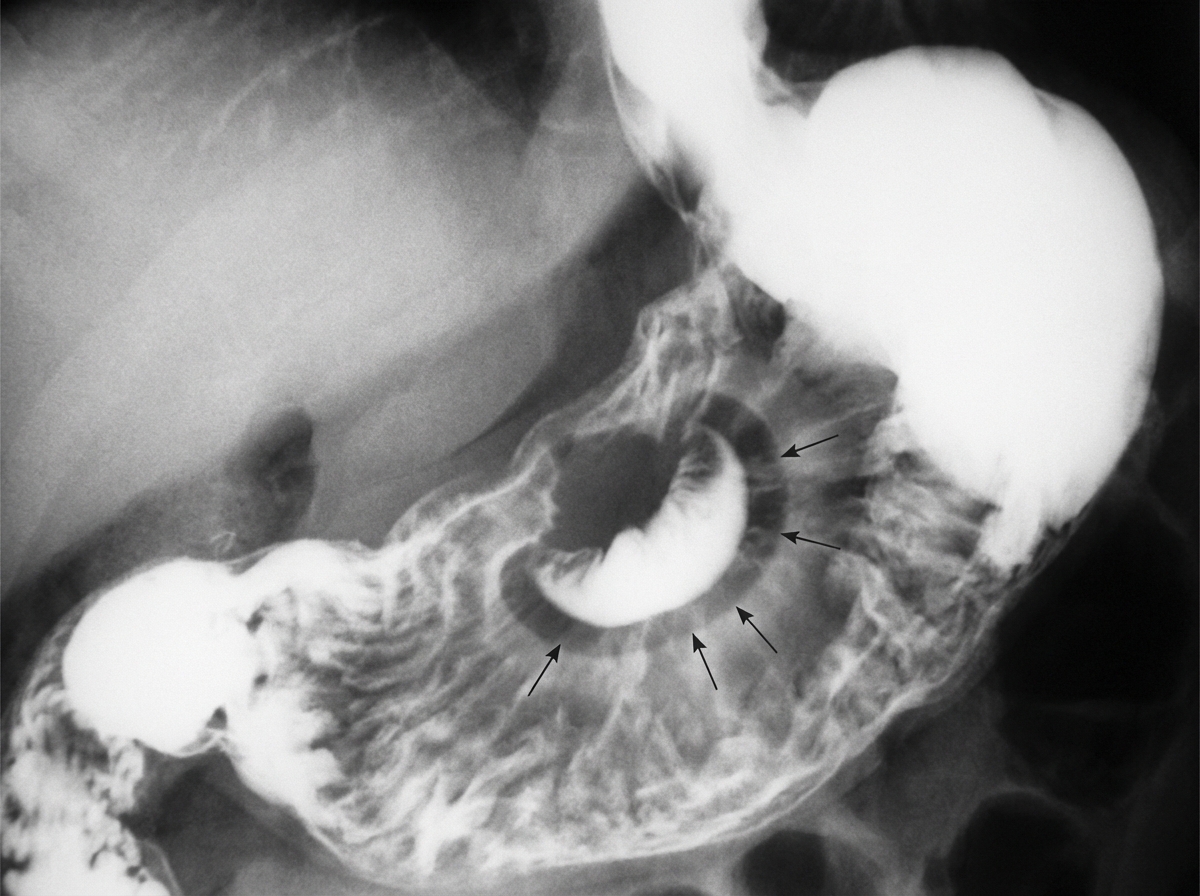

Explanation: ### Explanation **1. Why Crohn Disease is Correct:** The clinical presentation is classic for **Crohn Disease (CD)**. The patient is young (typical bimodal age distribution: 15–30 and 50–80 years) and presents with signs of **acute intestinal obstruction** and inflammation (fever, tachypnea). Key diagnostic features provided include: * **Transmural Inflammation:** Leads to the formation of **fistulas** (e.g., entero-enteric, as seen here) and **strictures** due to fibrosis. * **Skip Lesions:** "Numerous small bowel strictures" suggest the characteristic non-contiguous involvement. * **Right Lower Quadrant Mass:** Often represents "creeping fat," thickened bowel loops, or an inflammatory phlegmon/abscess involving the terminal ileum. **2. Why Other Options are Incorrect:** * **Adenocarcinoma:** While CD increases the risk of small bowel adenocarcinoma, it usually presents in older patients and typically as a single mass/stricture rather than multiple strictures and fistulas. * **Carcinoid Tumor:** These are the most common tumors of the appendix and ileum. While they can cause obstruction (via desmoplastic reaction), they do not typically cause fever or fistula formation. * **Pseudomembranous Colitis:** Caused by *C. difficile* toxin, it presents with profuse diarrhea and "volcano" lesions on colonoscopy. It involves the mucosa of the colon, not the small bowel, and does not cause strictures or fistulas. **3. NEET-PG High-Yield Pearls:** * **String Sign of Kantor:** Radiologic finding in CD due to terminal ileal strictures. * **Cobblestone Appearance:** Due to deep longitudinal and transverse ulcers. * **Histology:** Non-caseating granulomas (pathognomonic but seen in only ~50% of cases). * **Surgery:** Not curative; indicated only for complications (obstruction, fistula, perforation). The procedure of choice for multiple strictures is **Stricturoplasty** (to preserve bowel length).

Explanation: **Explanation:** The **'bird’s beak' appearance** is a classic radiological sign seen in **Sigmoid Volvulus**. This occurs when the sigmoid colon twists on its mesenteric axis, causing a high-grade mechanical obstruction. On a contrast enema (Barium enema), the contrast tapers at the site of the twist, resembling a bird's beak or an ace of spades. On a plain X-ray, this condition typically presents as a 'coffee bean' sign. **Analysis of Options:** * **Volvulus (Correct):** Specifically, sigmoid volvulus. The torsion creates a funnel-shaped narrowing at the point of the twist. * **Testicular torsion:** This is a urological emergency. While it involves twisting, the diagnosis is clinical or via Doppler ultrasound (showing absent blood flow), not a 'bird's beak' sign. * **Meconium ileus:** Associated with Cystic Fibrosis, it shows a 'soap bubble' appearance (Neuhauser sign) on X-ray due to air mixing with thick meconium in the terminal ileum. * **Ileal atresia:** Presents with multiple air-fluid levels and a 'triple bubble' sign (if high ileal) or microcolon on contrast enema. **NEET-PG High-Yield Pearls:** * **Sigmoid Volvulus:** Most common site of volvulus; associated with a high-fiber diet and chronic constipation. * **Management:** Sigmoidoscopic detorsion is the initial treatment of choice if there is no gangrene. * **Differential:** Achalasia Cardia also shows a 'bird's beak' appearance on a barium swallow due to the failure of the Lower Esophageal Sphincter (LES) to relax. * **Cecal Volvulus:** Shows a 'fetal lamb' or 'comma' sign on X-ray.